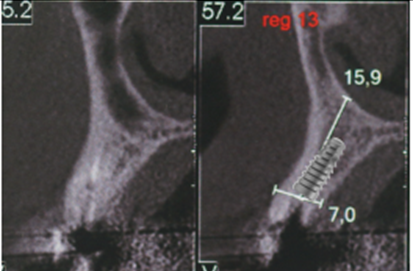

O caso clínico a seguir irá descrever o sucesso dessa nova realidade. Paciente J.C., de 65 anos de idade, do sexo masculino, compareceu em minha clínica com o elemento 13 fraturado (Figura 1). Após análise criteriosa da tomografia, foi planejada a exodontia e a instalação imediata do implante seguindo as novas tendências no posicionamento tridimensional, isto é, a melhor posição no rebordo na relação dento alveolar (Figura 2). Foi realizada a terapia medicamentosa com a administração de Amoxicilina 500 mg, de oito em oito horas durante sete dias, iniciando um dia antes do procedimento, e o uso de anti-inflamatório após a cirurgia, durante três dias. A exodontia foi realizada de forma atraumática, como sugerido na literarura (Figuras 3 e 4) e foi realizada a fresagem para a instalação de um implante Due Cone Implacil De Bortoli (conexão morse) de 3.5 x 13 mm, que foi estabilizado a 46 Ncm (Figuras 5, 6 e 7). Após a instalação, o gap foi preenchido com biomaterial, um cicatrizador de 5.5 X 3.5 mm (diâmetro/altura) foi instalado e o tecido foi suturado ao seu redor, protegendo assim o biomaterial (Figura 8).

Figura 2 – Planejamento do implante